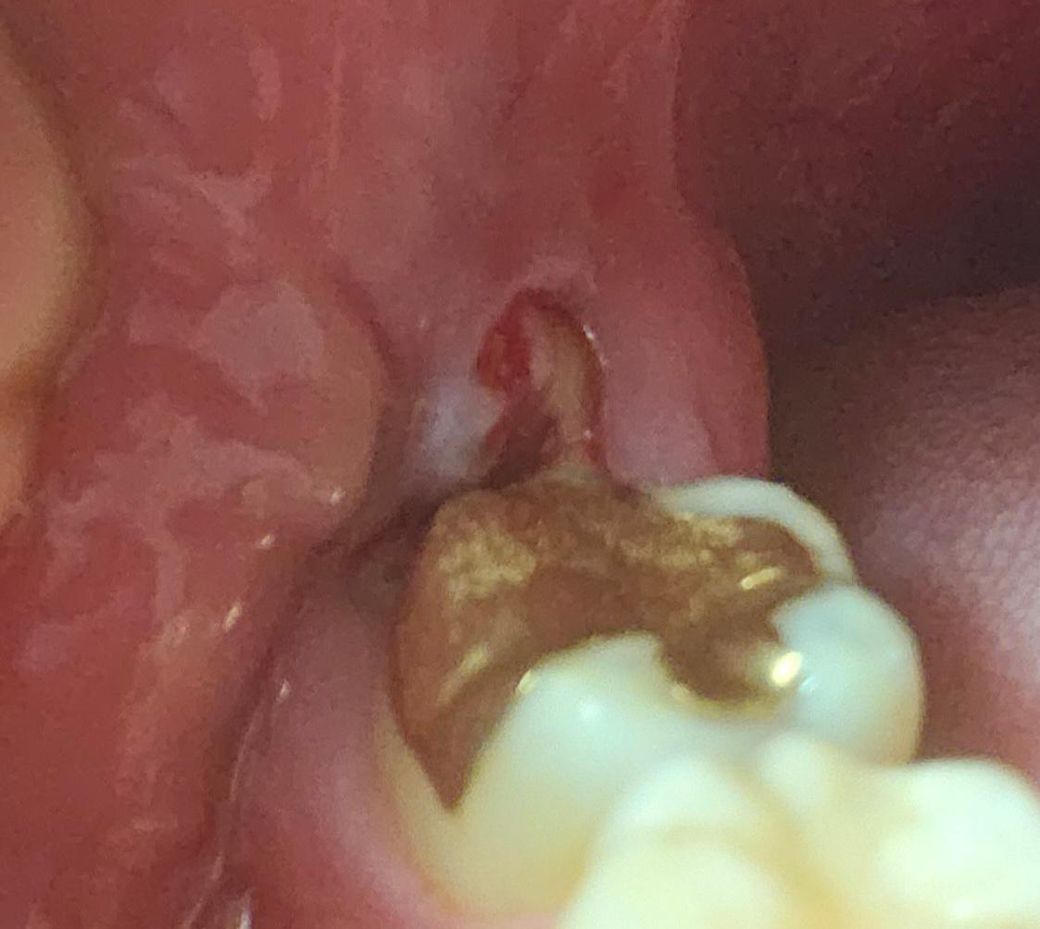

잇몸 염증이 한달사이 재발했는데 어떤 치료해야 할까요?

매복 사랑니 쪽에 염증이 한달 사이에 또 재발했는데 아무래도 재발,충치 방지위해 발치 해야겠죠?

잇몸이 저렇게 부어있어도 발치가 가능한지,

알보칠로 커버가 될지, 저정도 상태면 어느정도인지 궁금합니다!

• 1번 째 사진

사랑니로 인한 치관주위염입니다 사랑니 발치 안하면 재발가능성이 있습니다 온찜질, 항생제 복용으로 붓기 좀 가라앉히고 그 다음 발치합니다